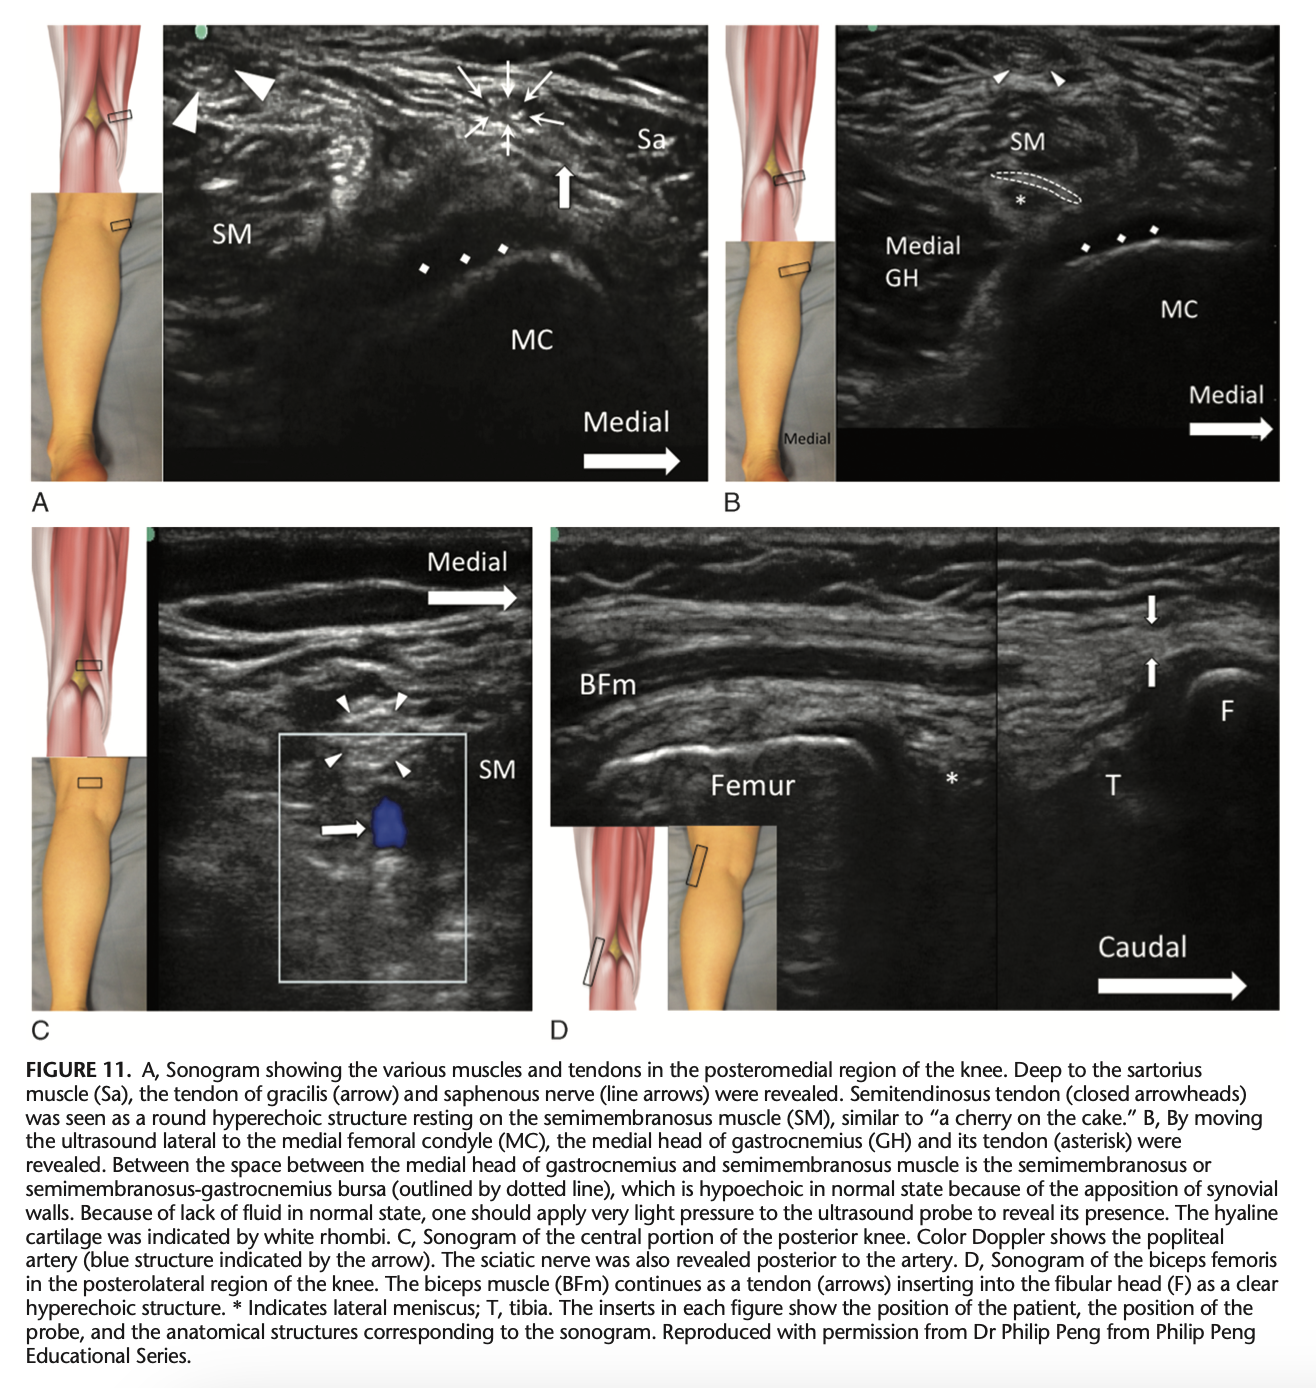

Which structures are seen from medial to lateral in the short-axis scan of the posterior knee?

A

Sartorius, gracilis, semimembranosus, semitendinosus, and medial head of gastrocnemius muscle.

Q

What is located between the tendons of semimembranosus and the medial head of gastrocnemius?

Semimembranosus or semimembranosus-gastrocnemius bursa.

What does the short-axis scan of the popliteal fossa reveal?

Neurovascular bundle and sciatic nerve (arrowheads).

What is examined in the long-axis scan when moving the probe laterally in the posterior knee?

Biceps femoris muscle and tendon.